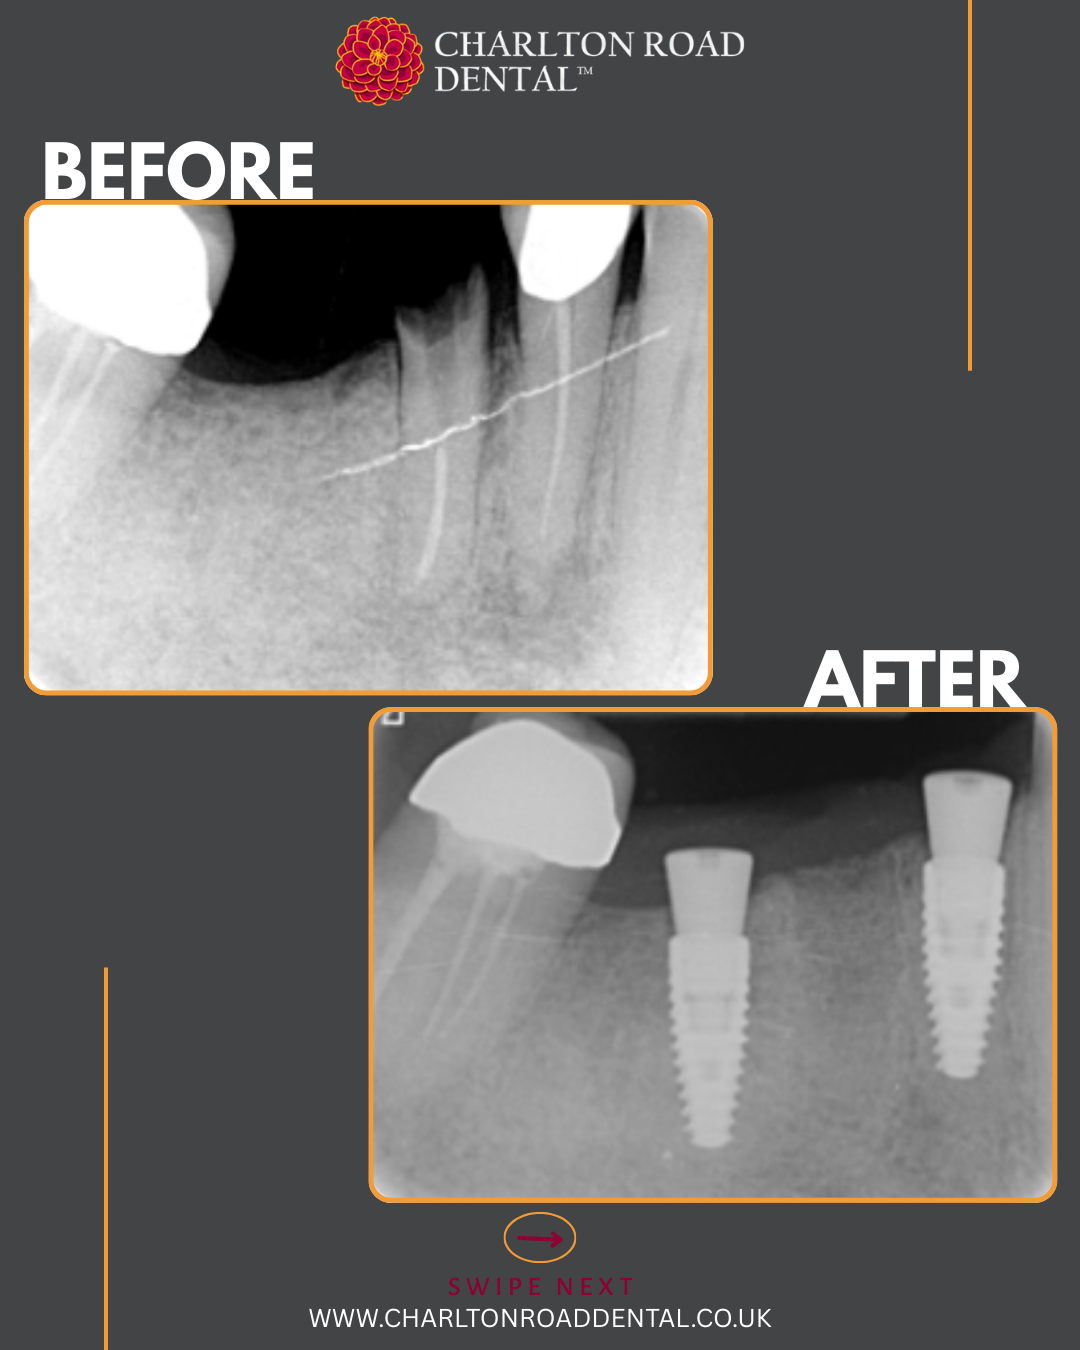

A week of implants @ Charlton Road Dental